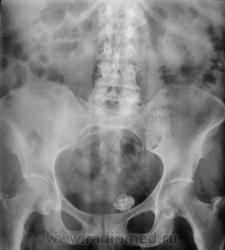

Обзорно.

Судя по костям пациентка в возрасте, думаю кальцификация миоматозного узла.

рак средне- и верхнеампулярного отделов прямой кишки; диверикулез сигмовидной кишки; миома матки

7. обызествленный узел матки стар как мир...

обызвествленный миоамтозный узел

у всех трех случаев очень похож характер обызвествления.